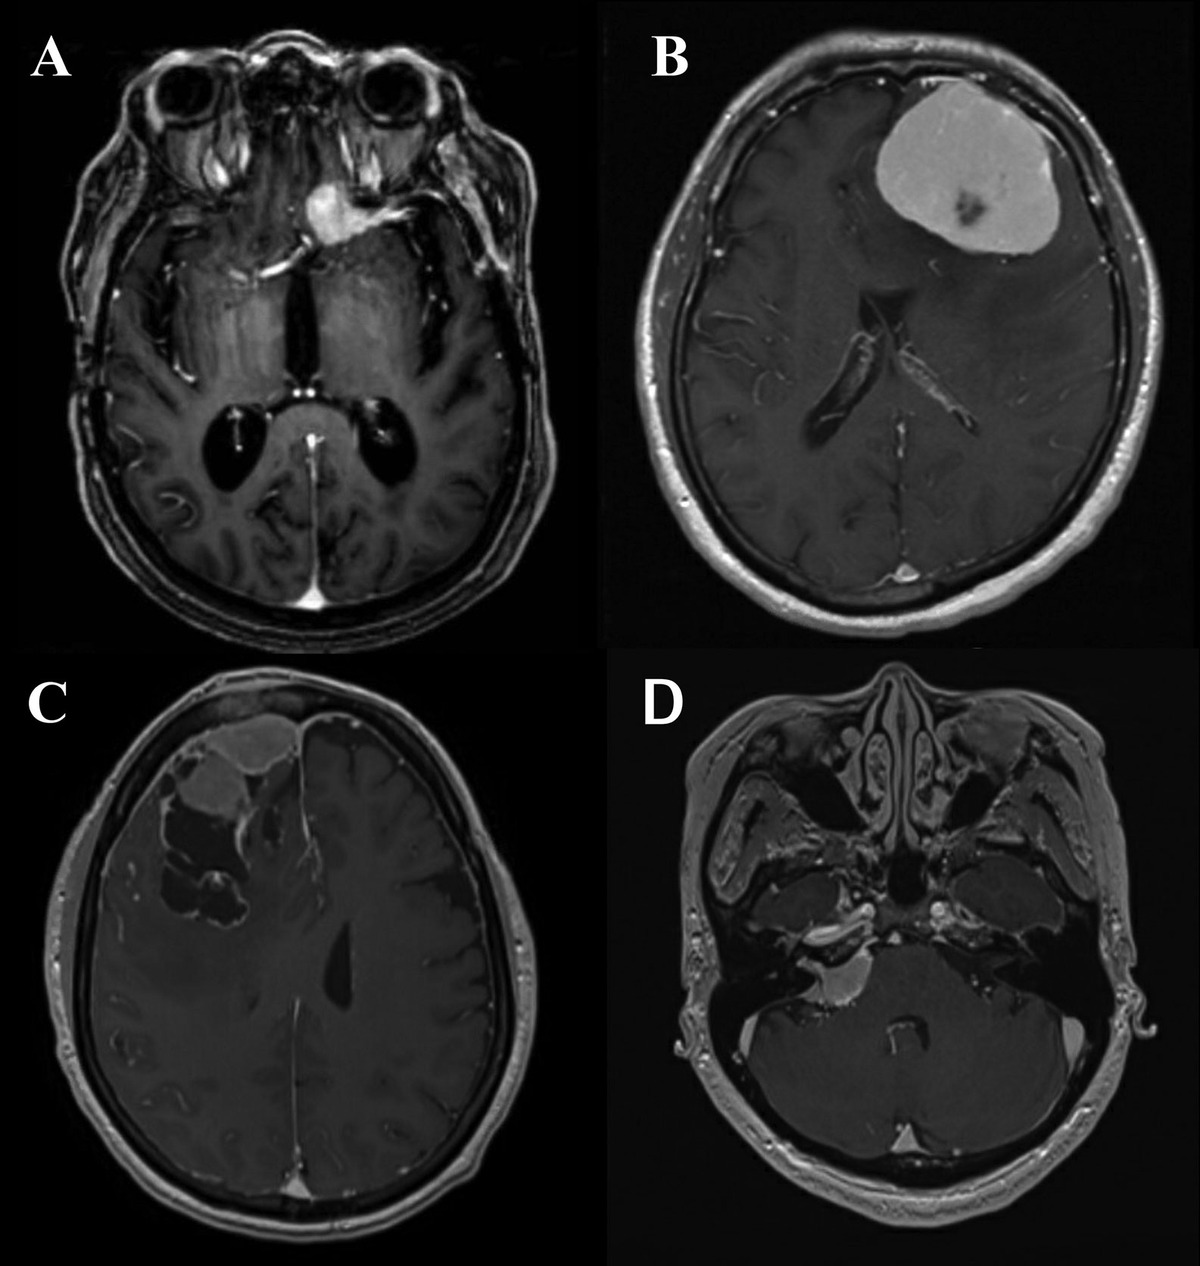

健康・医学 Meningiomas, Part II (Volume 170) i2 Meningiomas。Regression of Intracranial Meningiomas Following Treatment。Unveiling a Biomarker Signature of Meningioma: The Need for。Meningiomas, Part II (Volume 170) (Handbook of Clinical Neurology, Volume 170) ハードカバー – 2020/8/14英語版 Michael W. McDermott MD (編集)※中古品のため、使用できれば良いという方のみのご購入をお待ちしております。筋骨格系のキネシオロジー。※商品状態の少々の見落としはご理解下さい。骨形態計測ハンドブック/高橋栄明 著。※都合により発送方法を変更する場合があります。【美品・書き込みなし】精神薬理学エセンシャルズ/精神科治療薬の考え方と使い方。。The Evolving Classification of Meningiomas: Integration of。角に少々イタミあり。中古品のため、多少のスレ、イタミ等ありますが、書き込みなく、とても良好な状態です。気管支鏡テキスト 第3版。【美品】カパンジー機能解剖学(全3巻)。※値引交渉にはお答え致しません。※希少品の為、定価より高額の場合があります。常用カイロプラクティックマニュアル。【裁断済】スキル美容外科手術アトラス 眼瞼。【佐川急便/日本郵便から佐川急便/日本郵便及びその逆等】※ビニールにて梱包し発送致しますが、保管、輸送によるイタミ等はご容赦下さい。※コメント不要、即購入にてご注文お願いします。早わかり犬と猫の臨床 小動物臨床ハンドブックシリーズ 5

16153-9/asset/2fac6123-c7b5-4672-9706-47561c05fa86/main.assets/gr2_lrg.jpg)